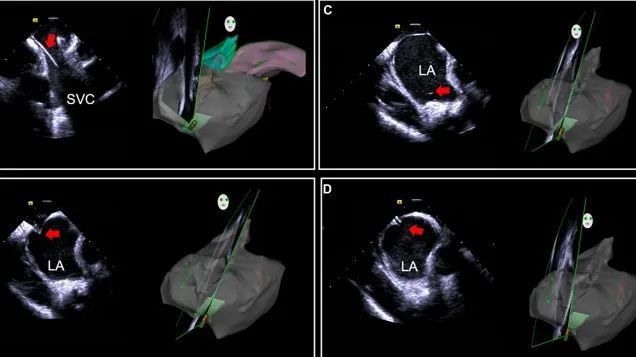

一種與心導(dǎo)管檢查相結(jié)合的超聲心動圖診斷新興技術(shù),通過將超聲探頭置于心腔內(nèi)部,發(fā)射并接收超聲信號,來精確獲取心臟解剖結(jié)構(gòu)、心臟血流動力學(xué)等信息的實時成像。與其他影像技術(shù)相比,ICE技術(shù)具有操作簡單、無輻射、安全性高、手術(shù)效率高、實用等優(yōu)勢,ICE在很大程度上有望取代經(jīng)食道超聲心動圖(TEE),成為電生理和結(jié)構(gòu)性心臟病領(lǐng)域的理想成像方式。

目前ICE技術(shù)已被應(yīng)用于左心耳封堵、房顫射頻消融、二尖瓣成形、房間隔缺損封堵等多種心臟介入手術(shù),應(yīng)用場景主要圍繞臟電生理、結(jié)構(gòu)性心臟病等領(lǐng)域,目前以電生理應(yīng)用為主。數(shù)據(jù)顯示,我國結(jié)構(gòu)性心臟病介入器械市場規(guī)模已從2017年的4億元增長至2021年的20億元,年復(fù)合增長率達48.3%;預(yù)計到2025年,該市場規(guī)模將達到104億元,可以預(yù)見ICE市場規(guī)模也將同步高速增長,未來市場發(fā)展空間廣闊。

心腔內(nèi)超聲(ICE)技術(shù)壁壘極高,國內(nèi)主要廠商核心部件仍舊為進口,集成了超聲和圖像處理最前端技術(shù),包括超聲探頭、線纜、軟件成像算法等,是當(dāng)前內(nèi)窺超聲方向最具挑戰(zhàn)的領(lǐng)域。ICE的應(yīng)用經(jīng)歷了2D平面成像、3D三維立體成像、以及4D的實時三維立體成像階段。